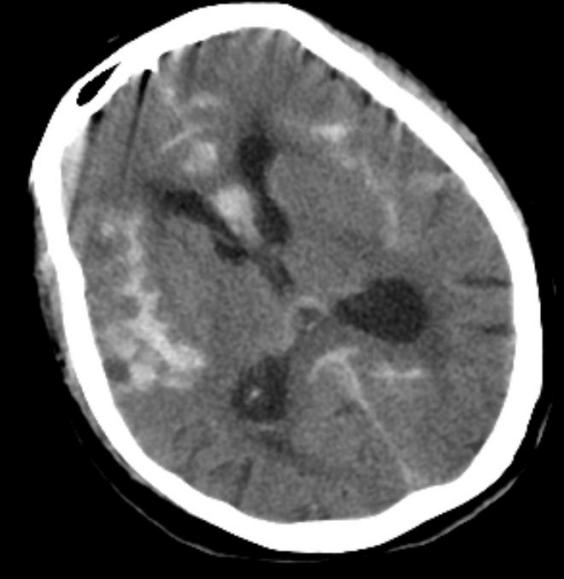

赵女士今年已85岁高龄,患高血压病已30余年,冠心病10余年,曾置入5枚冠状动脉支架,平时可自理。7月8日晚间在家中洗澡时突发剧烈头痛,伴恶心呕吐,紧急来到北京市垂杨柳医院急诊内科就诊。经为患者行头颅CT检查提示蛛网膜下腔出血,急诊当即请神经外科会诊。神经外科值班医生刘耀东赶到急诊,查看患者呈嗜睡状态,颈项强直。紧急为患者安排了头颈动脉CTA检查,显示前交通动脉瘤。

头颅CT显示广泛蛛网膜下腔出血,脑室积血